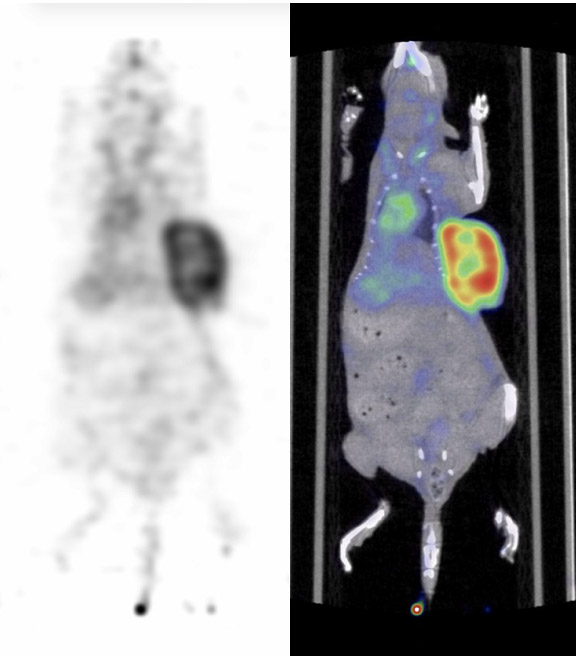

CASE 4: Rat PET/CT imaging with 18F-FDG

• Courtesy of: D.Panetta and P.A. Salvadori, IFC-CNR Pisa, Italy

Research objective:Rat PET/CT imaging with F18-FDG for accessing brain and heart uptake

Animal model:Wistar rat, 294g

Acquisition protocol:PET: 15 min acquisition time, 1 bed position; CT: 20 s acquisition time, 1 bed position, 80 kVp, 1 mA

Processing and reconstruction protocol:PET: 3D-OSEM, 0.42 x 0.42 x 0.855 mm voxel size; CT: 0.08 mm isotropic voxel size

Biomarker or contrast agent:18F-FDG, activity: 200 uCi, volume: 0.3 mL, imaging at 60 min post injection